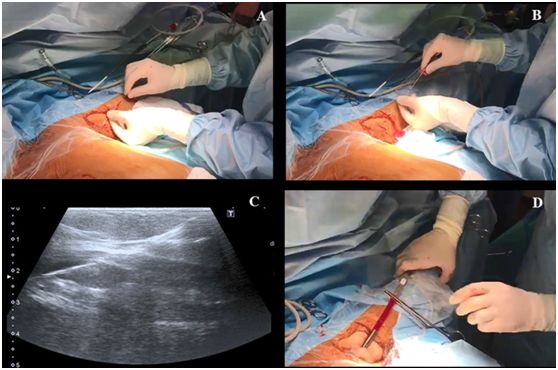

当在腋静脉腔内观察到针尖的斜面时(一个白点),可以很容易地确定穿刺针在血管内的位置(图2C)。也可以通过回抽血液1-2ml来确认穿刺针的位置是在静脉内。当患者血压较低时,无搏动性血流出现并不能排除穿刺到动脉的可能。随后置J形导丝,导丝的位置也可能在超声实时下确认(图3,A-C)。也可以通过颈部超声探查来排除导丝进行左侧颈内静脉。导丝置入长度应限定在20cm,以避免引起心律失常。随后扩张皮肤穿刺点,用Seldinger技术置入导管。在输注任何液体之前,回抽确认导管远端是否在血管腔内,随后再用肝素盐水冲洗导管。导管置入深度为20cm。

图3,A和B置入导丝,C超声视窗下可见静脉的导丝;D 把导管固定